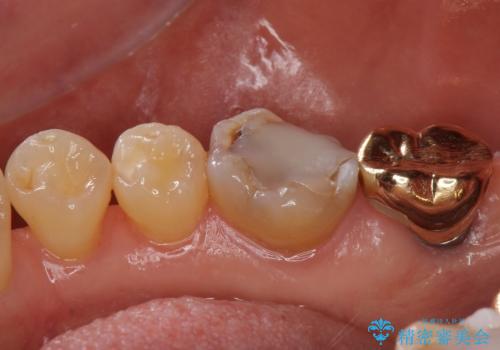

- 昔つめた材料が欠けたこと、歯の捻転を主訴に来院されました。

矯正治療の希望はなかったため、被せ物で歯の形を修正することになりました。

クラウンでは歯のがたつきを修正することもできます。

虫歯の除去と歯の捻転の両方を解決することができました。